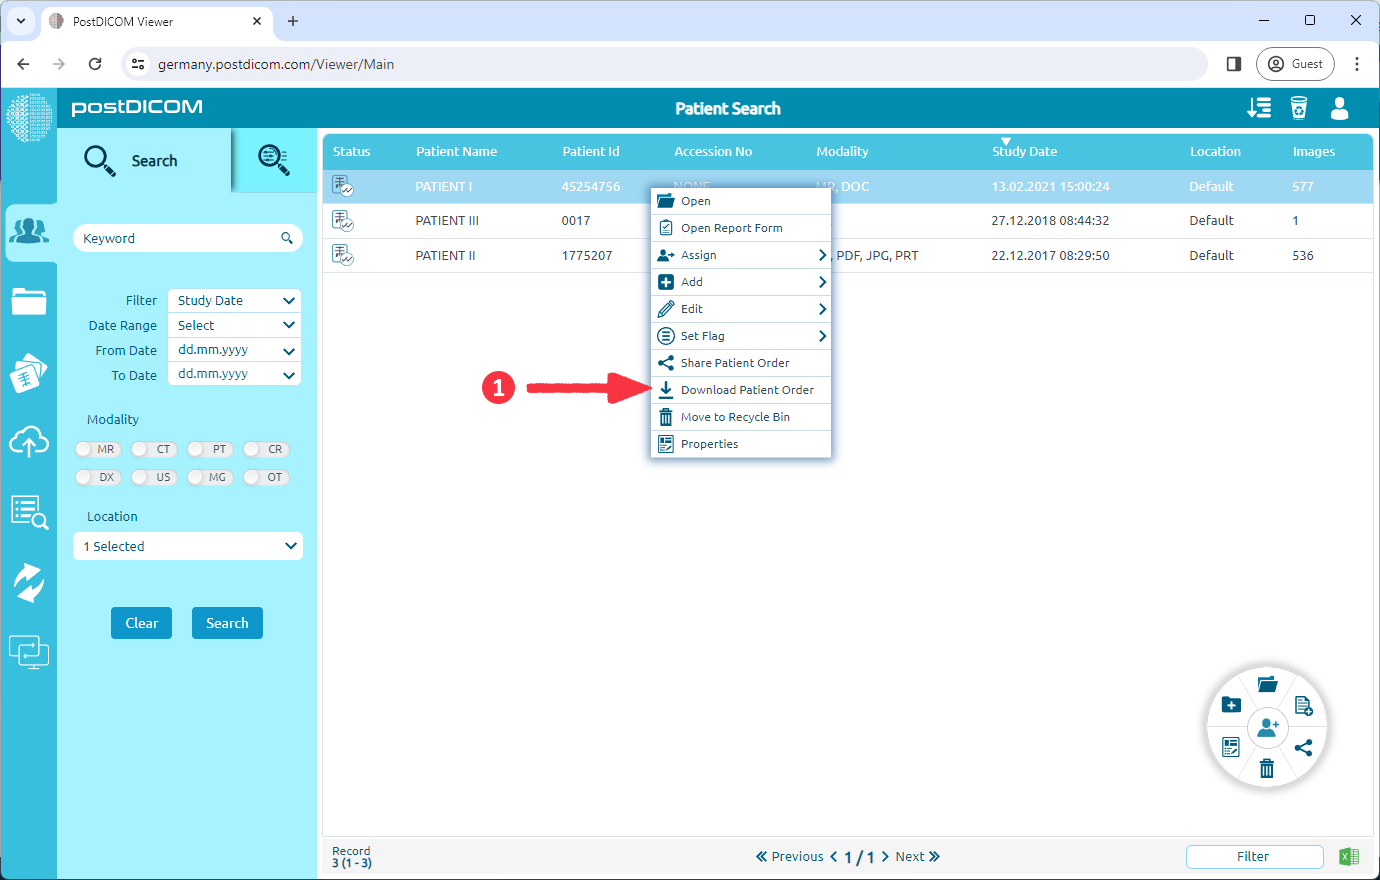

To download images with CD Viewer, right-click on the patient study that you want to download and select "Download Patient Order" on context menu.